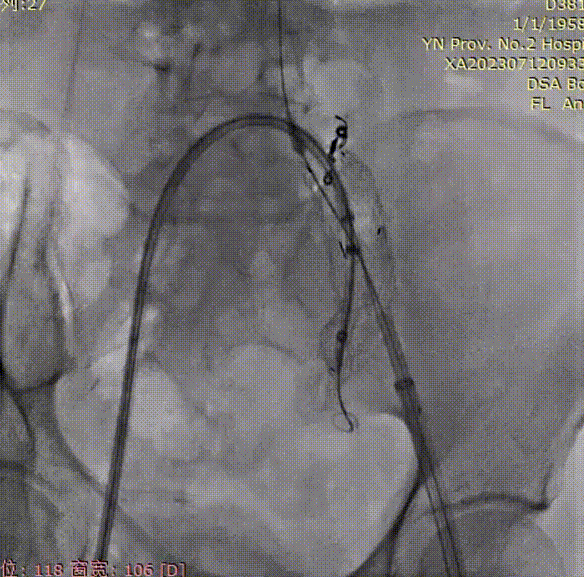

从右侧顺着牵张导丝,将戈尔DSF1245 导引鞘(翻山鞘)推送至左侧IBE主体短腿内,接下来超选髂内,建立髂内通路植入髂内支架;

gore医疗怎么样「漫腹精论」双股动脉入路,纯腔内保双髂——GORE® EXCLUDER® 髂动脉分支型覆膜支架(IBE)治疗双侧髂总动脉_https://www.jmylbn.com_新闻资讯_第16张

导管内手推造影,确认左髂内超选成功;